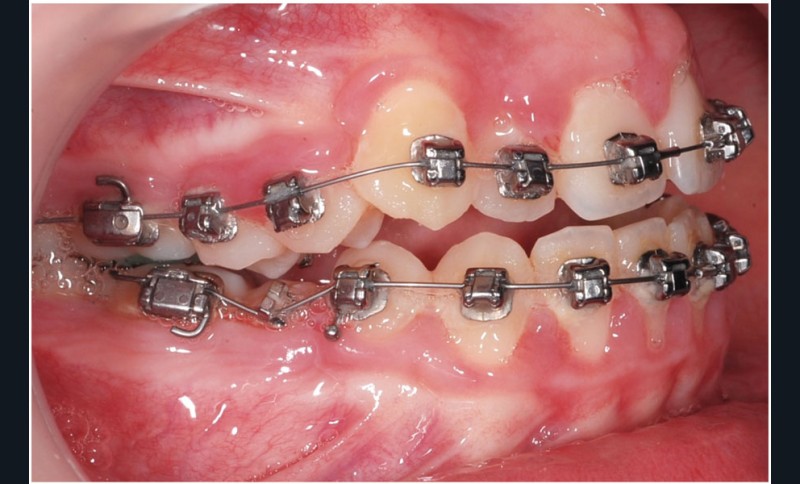

Le cas d’Anthony âgé de 11 ans et 7 mois qui présente une endomaxillie bilatérale associée à un léger encombrement mandibulaire dans un contexte de classe I squelettique hyperdivergente (fig. 1 à 10) est très représentatif de ce que peuvent apporter les forces légères appliquées aux alvéoles dentaires tout en intégrant des torques spécifiques qui permettent de contrôler parfaitement l’orientation radiculaire (fig. 11 à 29).

Le système laisse beaucoup de liberté dans l’interface entre bracket et arc : la vascularisation, et donc le recrutement cellulaire et la reconstruction osseuse s’en trouvent améliorés, la mise en place de l’occlusion se fait sous le contrôle de la matrice fonctionnelle, car les forces engagées restent en dessous de la puissance des forces masticatrices notamment.